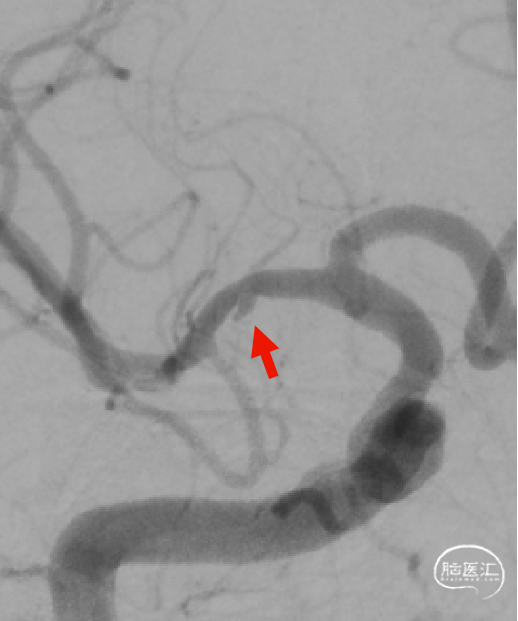

DSA:DSA提示右侧颈内动脉C6段可见多发动脉瘤。

术前诊断:右侧颈内动脉C6段多发动脉瘤。

治疗方案:血流导向装置植入术。

载瘤动脉远端血管直径:4.0mm

载瘤动脉近端血管直径:4.9mm、4.5mm(两个角度)